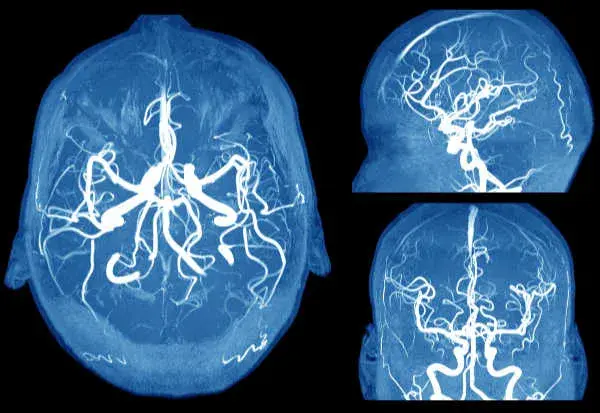

Detención de aneurisma cerebral en la DRPAD

Detención de aneurisma cerebral en la DRPADRecordemos las indicaciones de detección de aneurisma cerebral en la DRPAD